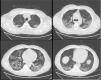

In order to reduce bio-aerosol dispersion, a surgical mask was placed over the patient’s mouth and nose.1Fig. 1 shows bilateral consolidations with ground-glass areas, mainly in the posterior dependent zones on CT-scan. Based on this radiological picture, we continued NHF in awake prone positioning. Fig. 2 illustrates oxygen pulse saturation/FiO2 (SpO2/FiO2), oxygen blood pressure/FiO2 (PaO2/FiO2) ratios and ROX index trends within the first four days of treatment. ROX index is defined as the ratio of pulse oximetry/fraction of inspired oxygen to respiratory rate (RR). This index, described by Roca et al.,2 identifies patients at risk of NHF failure. In particular, a ROX index of 4,88 is associated with a high risk of intubation. In conclusion, NHF setting was adjusted according to the maximum patient’s comfort and the best effects in terms of distending pressure and FiO2 stability. FiO2 was also targeted to achieve oxygen saturation between 94–96%. Prone positioning was implemented because we felt that the mild distension pressure generated by NHF could be enhanced by placing the ventilated areas in a dependent position, leading to increased V/Q mismatch.3